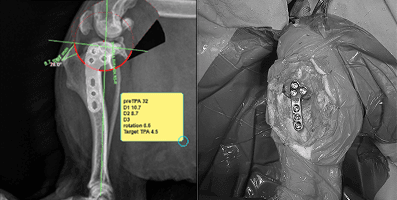

끊어진 인대를 임시로 봉합하는 방식이 아니라, TPLO/TTA와 같은 정형외과적 안정화 수술로 무릎 관절의 역학 구조를 교정해 인대가 없어도 관절이 흔들리지 않는 근본적인 안정성을 만들기 때문입니다.

관절을 잡아주는 인대가 손상되면 관절이 흔들리고, 연골 및 반월상연골 손상이 동반될 수 있습니다. 활동량과 관절 구조를 함께 고려해야 합니다.